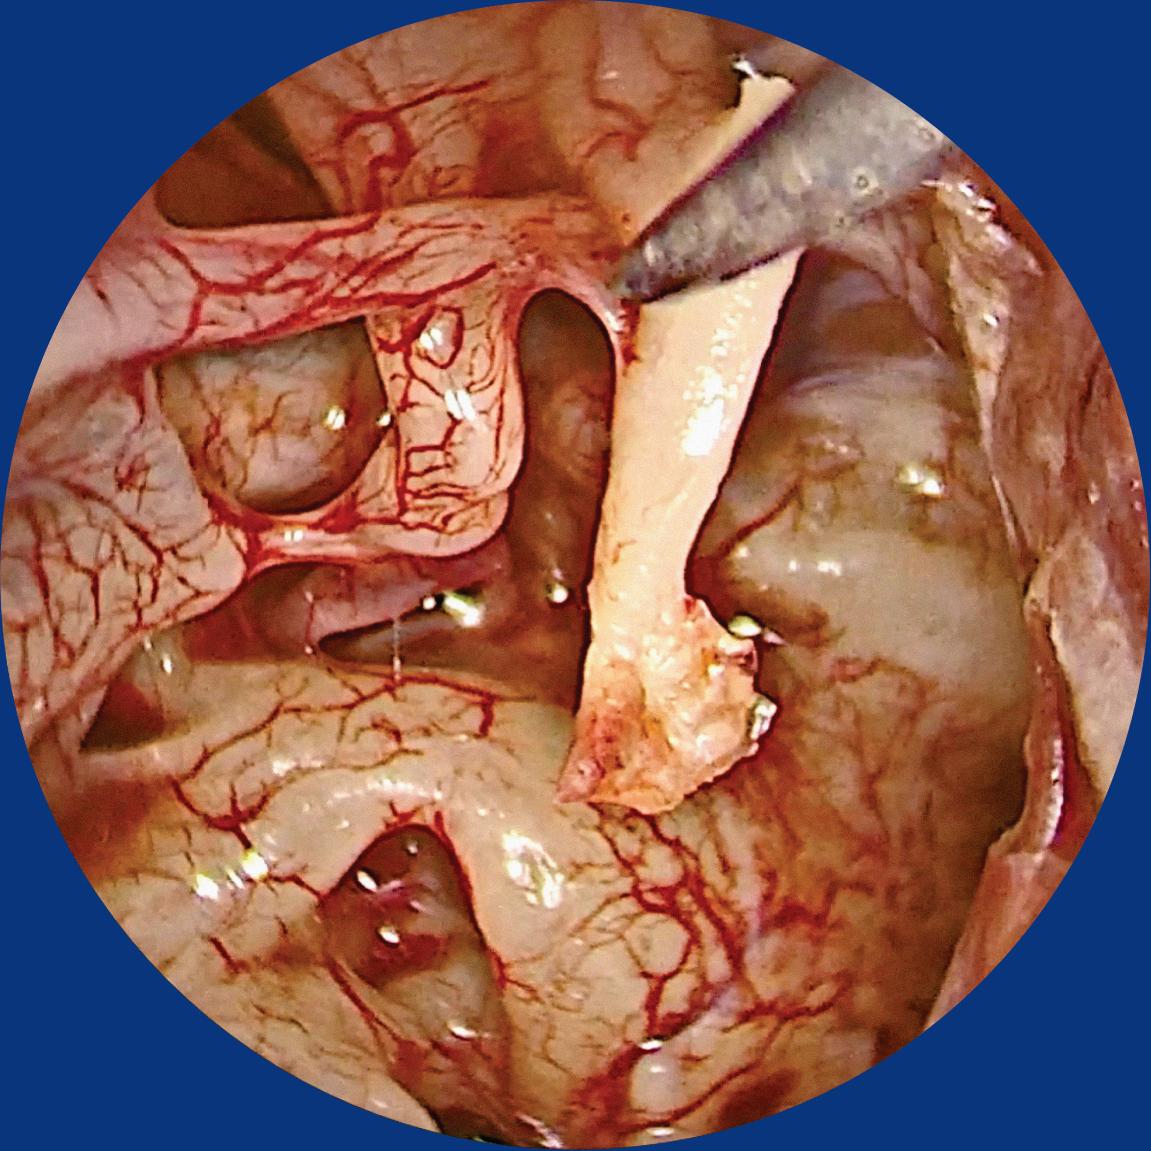

e) Os endoscópios de 45° ou 75° podem ser usados em abordagens do meato acústico interno em inspeção do mesmo no final de otoneurocirurgia (Fig. 1-2c,d).

Fig. 1-2. Visualização endoscópica da orelha média esquerda com ópticas de angulações diferentes.

(a) 0°. (b) 30°. (c) 45°. (d) 70°. EMP, eminência piramidal; NJR, nicho janela redonda; NF, nervo facial; P, promontório; PL, platina; TTE, tendão tensor do tímpano.